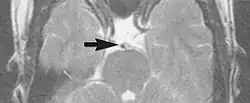

Flow can manifest as either an altered intravascular signal (flow enhancement or flow-related signal loss), or as flow-related artifacts (ghost images or spatial misregistration). Flow enhancement, also known as inflow effect, is caused by fully magnetised protons entering the imaged slice while the stationary protons have not fully regained their magnetization.[1] The fully magnetized protons yield a high signal in comparison with the rest of the surroundings. High velocity flow causes the protons entering the image to be removed from it by the time the 180-degree pulse is administered. The effect is that these protons do not contribute to the echo and are registered as a signal void or flow-related signal loss (Fig. 2).[1] Spatial misregistration manifests as displacement of an intravascular signal owing to position encoding of a voxel in the phase direction preceding frequency encoding by time TE/2.The intensity of the artifact is dependent on the signal intensity from the vessel, and is less apparent with increased TE.[1]